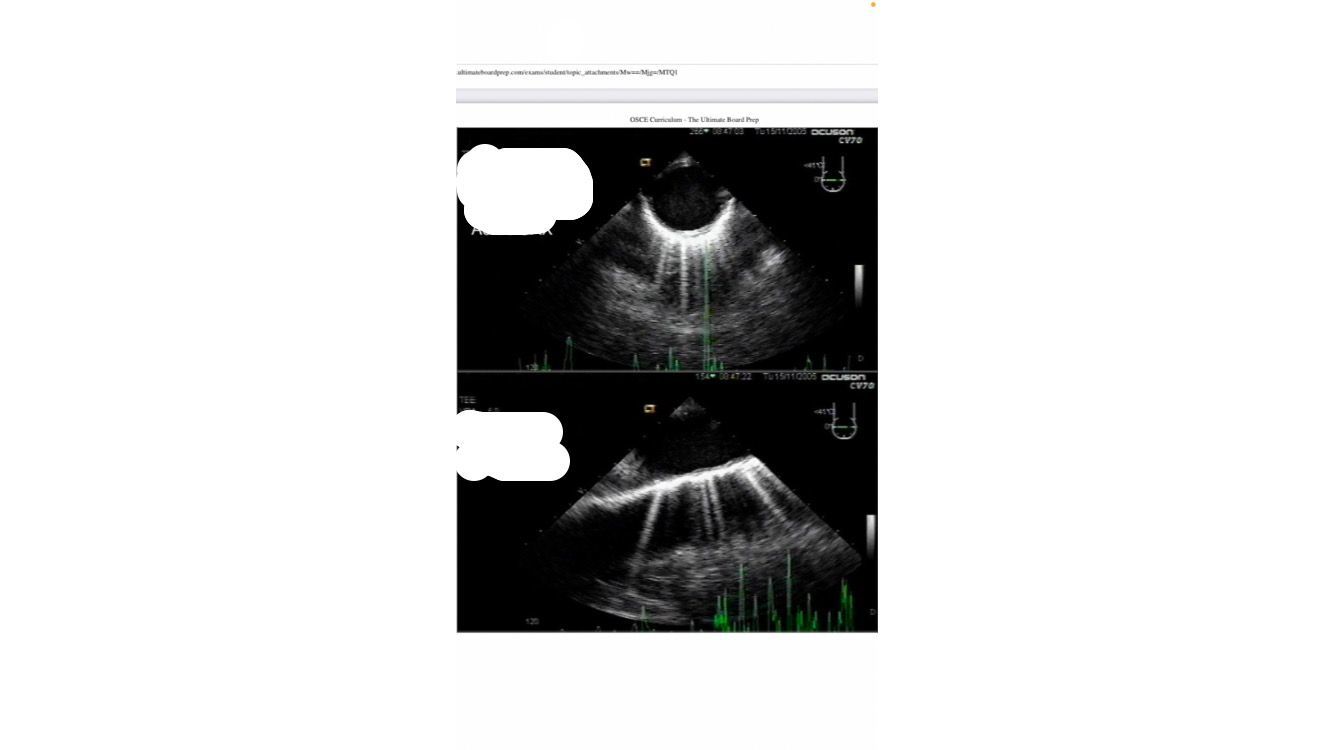

TTE IMAGE OF TAMPONADE